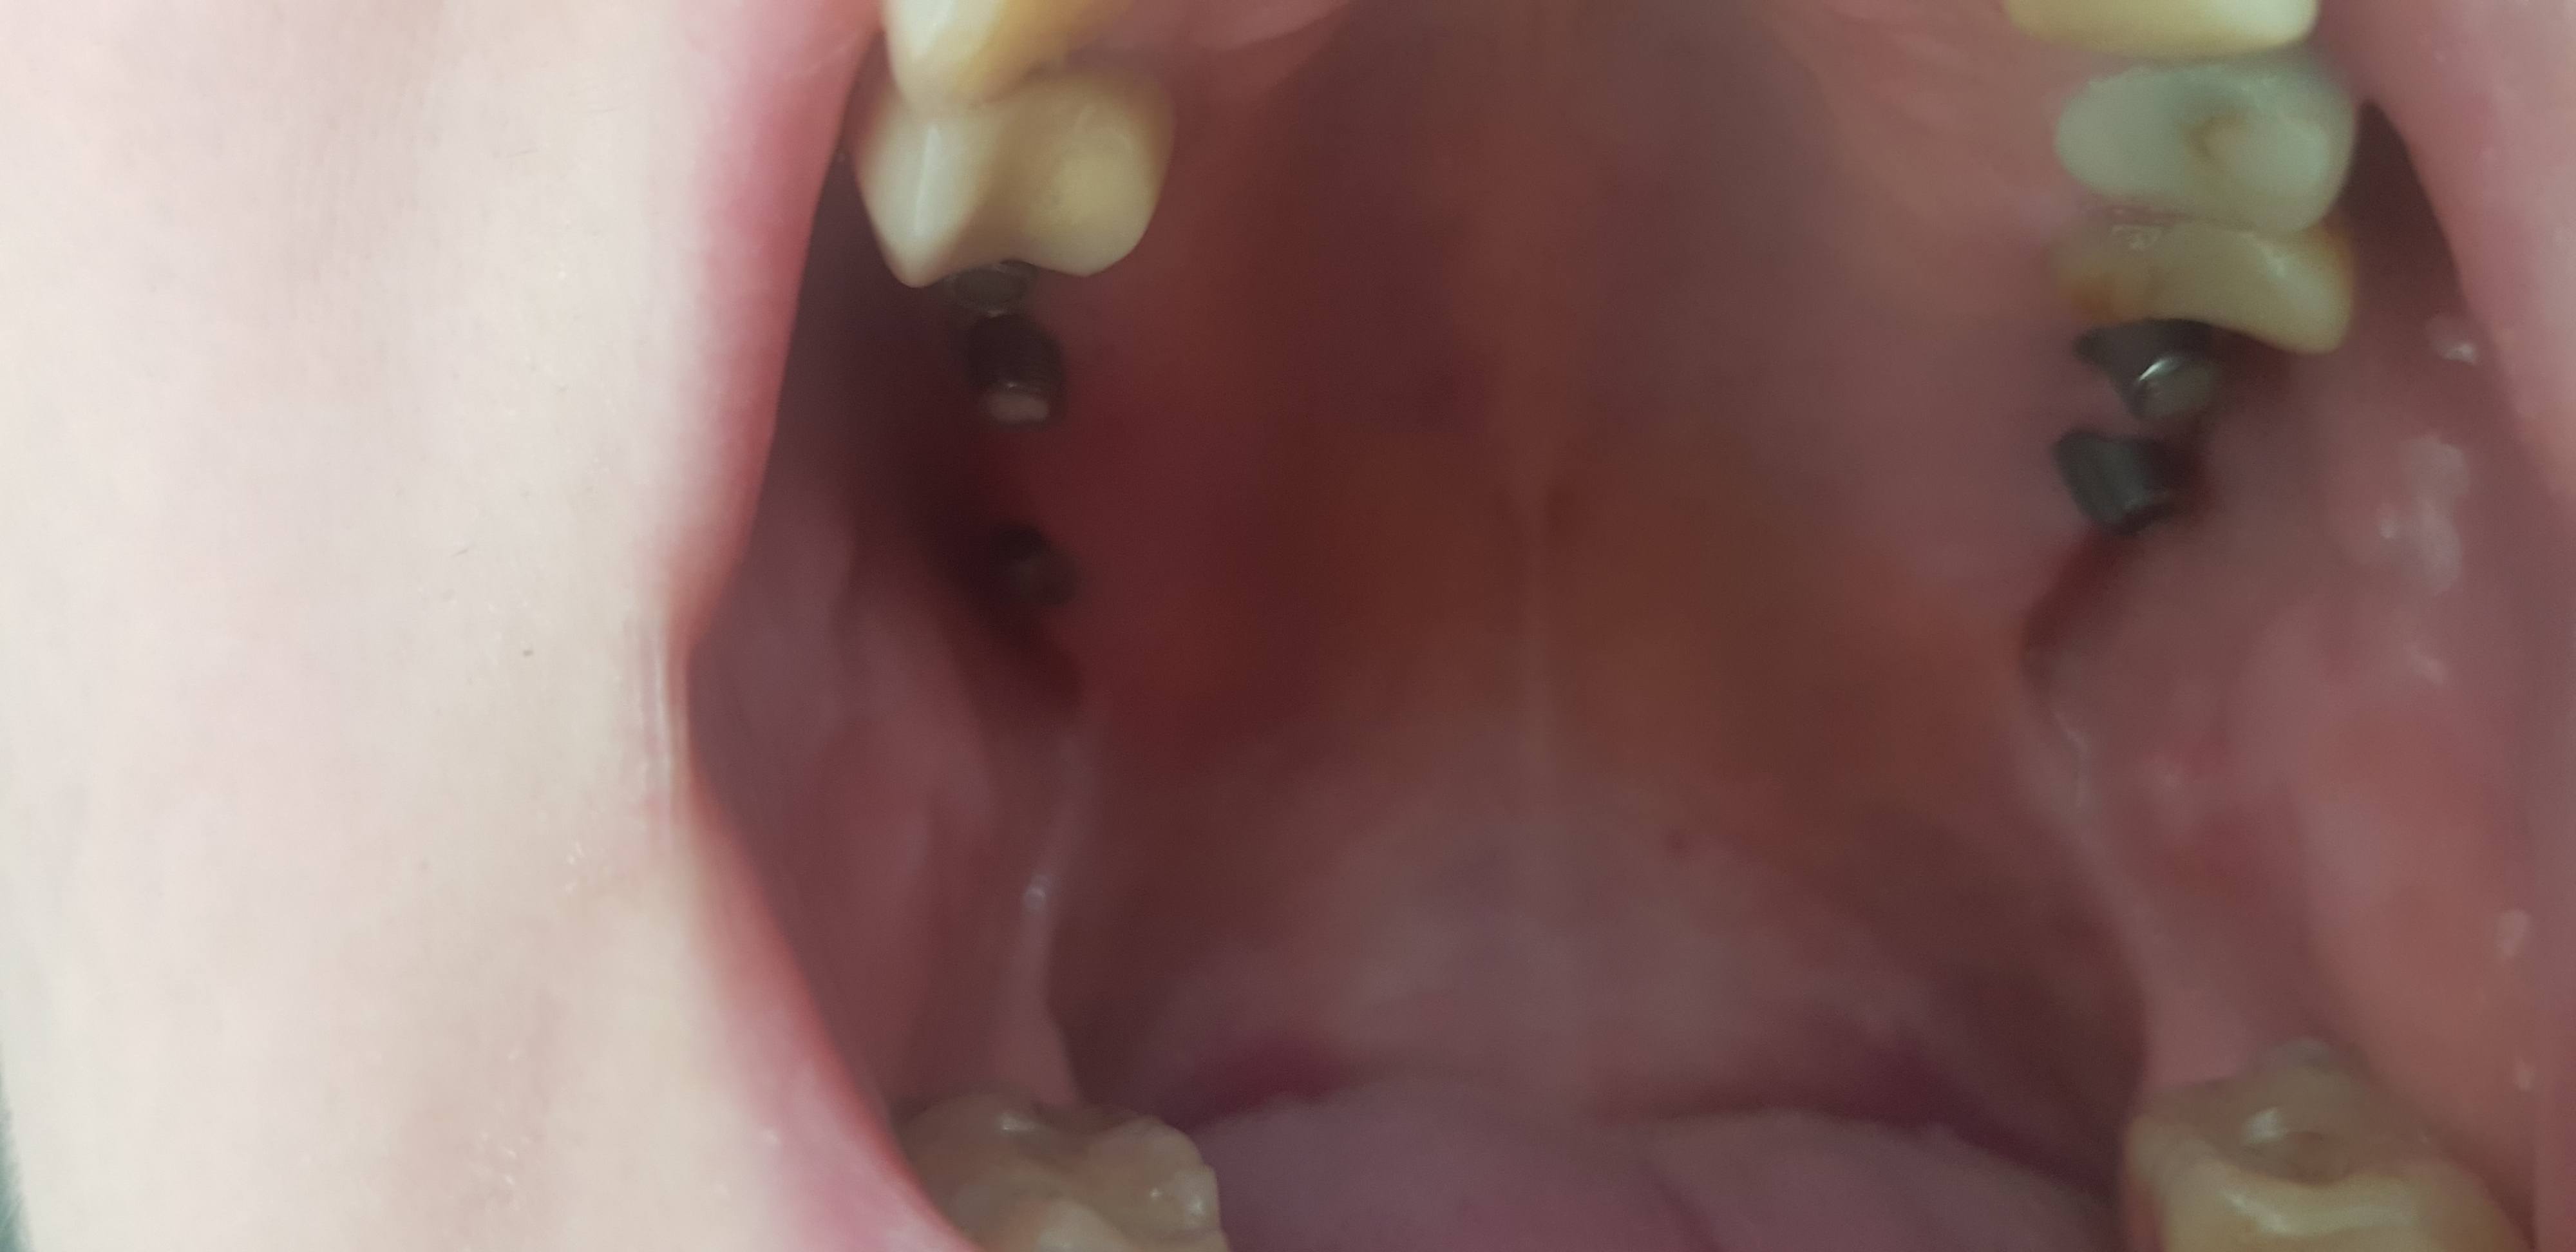

Зубы я лечила как положено, раз в полгода у стоматолога. В итоге, операция по извлечению пломбировочного материала из пазух носа, потеря 2 зубов. Остальные мне лечили так усердно, что сломали, инфицировали и другое. Наверное, врачи несут частичную ответственность, а также гены, но мне от этого не легче. В итоге7 имплантов, остальное нуждается в коронках, либо они уже стоят лет 15. Сумма внушительная, в районе 750 000. У меня нет денег даже хлеба купить себе, своих денег. Муж у меня добрый, но не богатый человек.

Импланты, где была резекция пахузи, болят… странно, правда, а болят, горло воспалено, нос течёт. Меня мучает постоянная температура 37.2-37.5.